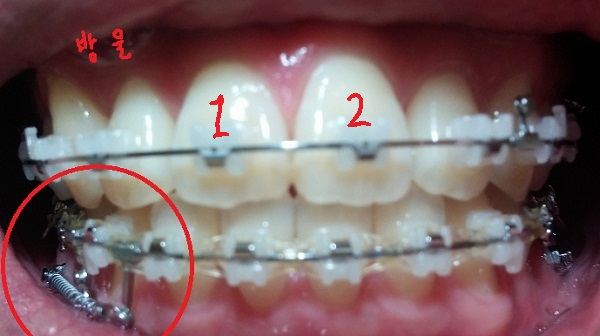

치료내용

-하악 파워체인 엇갈려서 걸어놓기(후기 23화와 같은 치료),

-하악 스프링 + 덧대기(잇몸이 눌리지 않게)

-고무줄착용하기(전 치료와 동일)

현재 교정진행상태

-중심선 99% 맞은 상태!!

-하악 파워체인으로 치아끼리 꽉 조여서 마무리로 가는 중!!

-일회용 고무줄로 치아를 다물 때, 뜨는 공간이 없게

상악 송곳니와 하악 송곳니를 당기는 중!!

[정면]

[스프링 정면]

[스프링 옆면]

+스프링사이에 또 다른 쇠기둥 보이시죠?! 저건 스프링이 잇몸에 닿아서 짓눌리지 않게 하기 위해서 해둔 조치랍니다.(제가 눌려서 아프다고 호소했더니 저런 방법으로 해주셨어용^^)